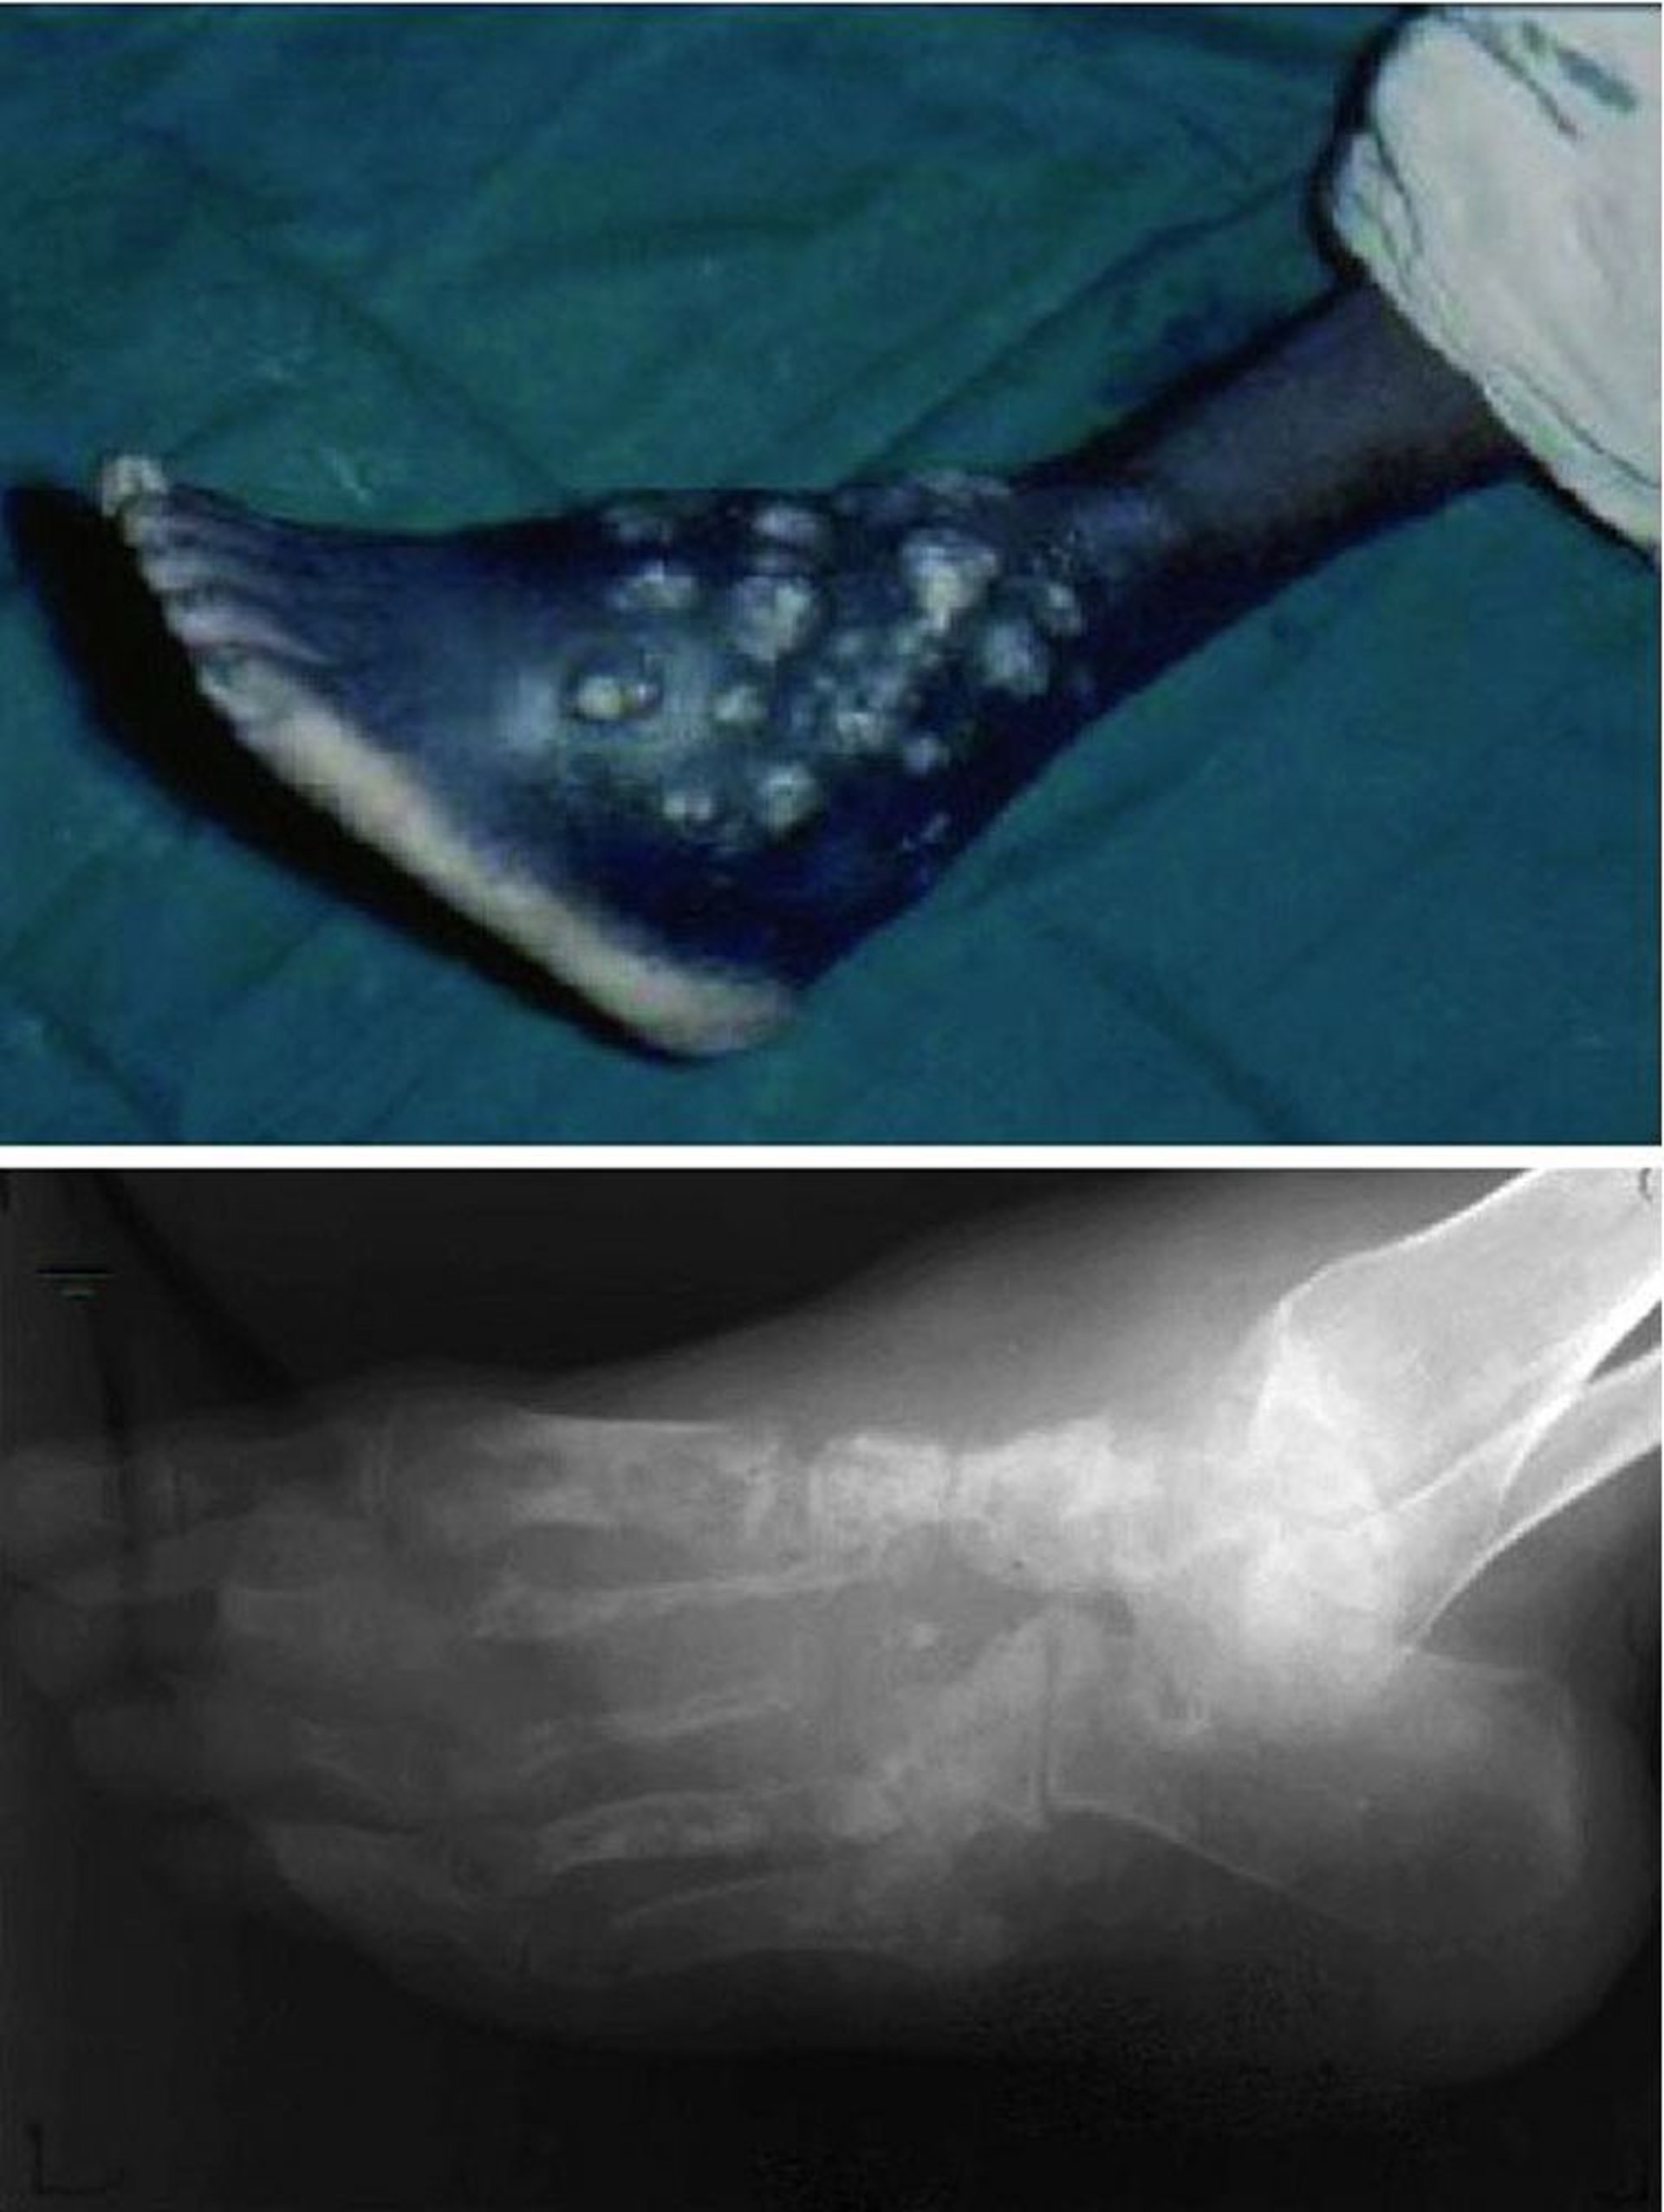

U nấm (bàn chân Madura)

Ảnh này cho thấy các vết thương mạn tính, không lành kèm theo các đợt chảy dịch và loét tái phát (trên) và tình trạng phá hủy toàn bộ cấu trúc xương của bàn chân (dưới).